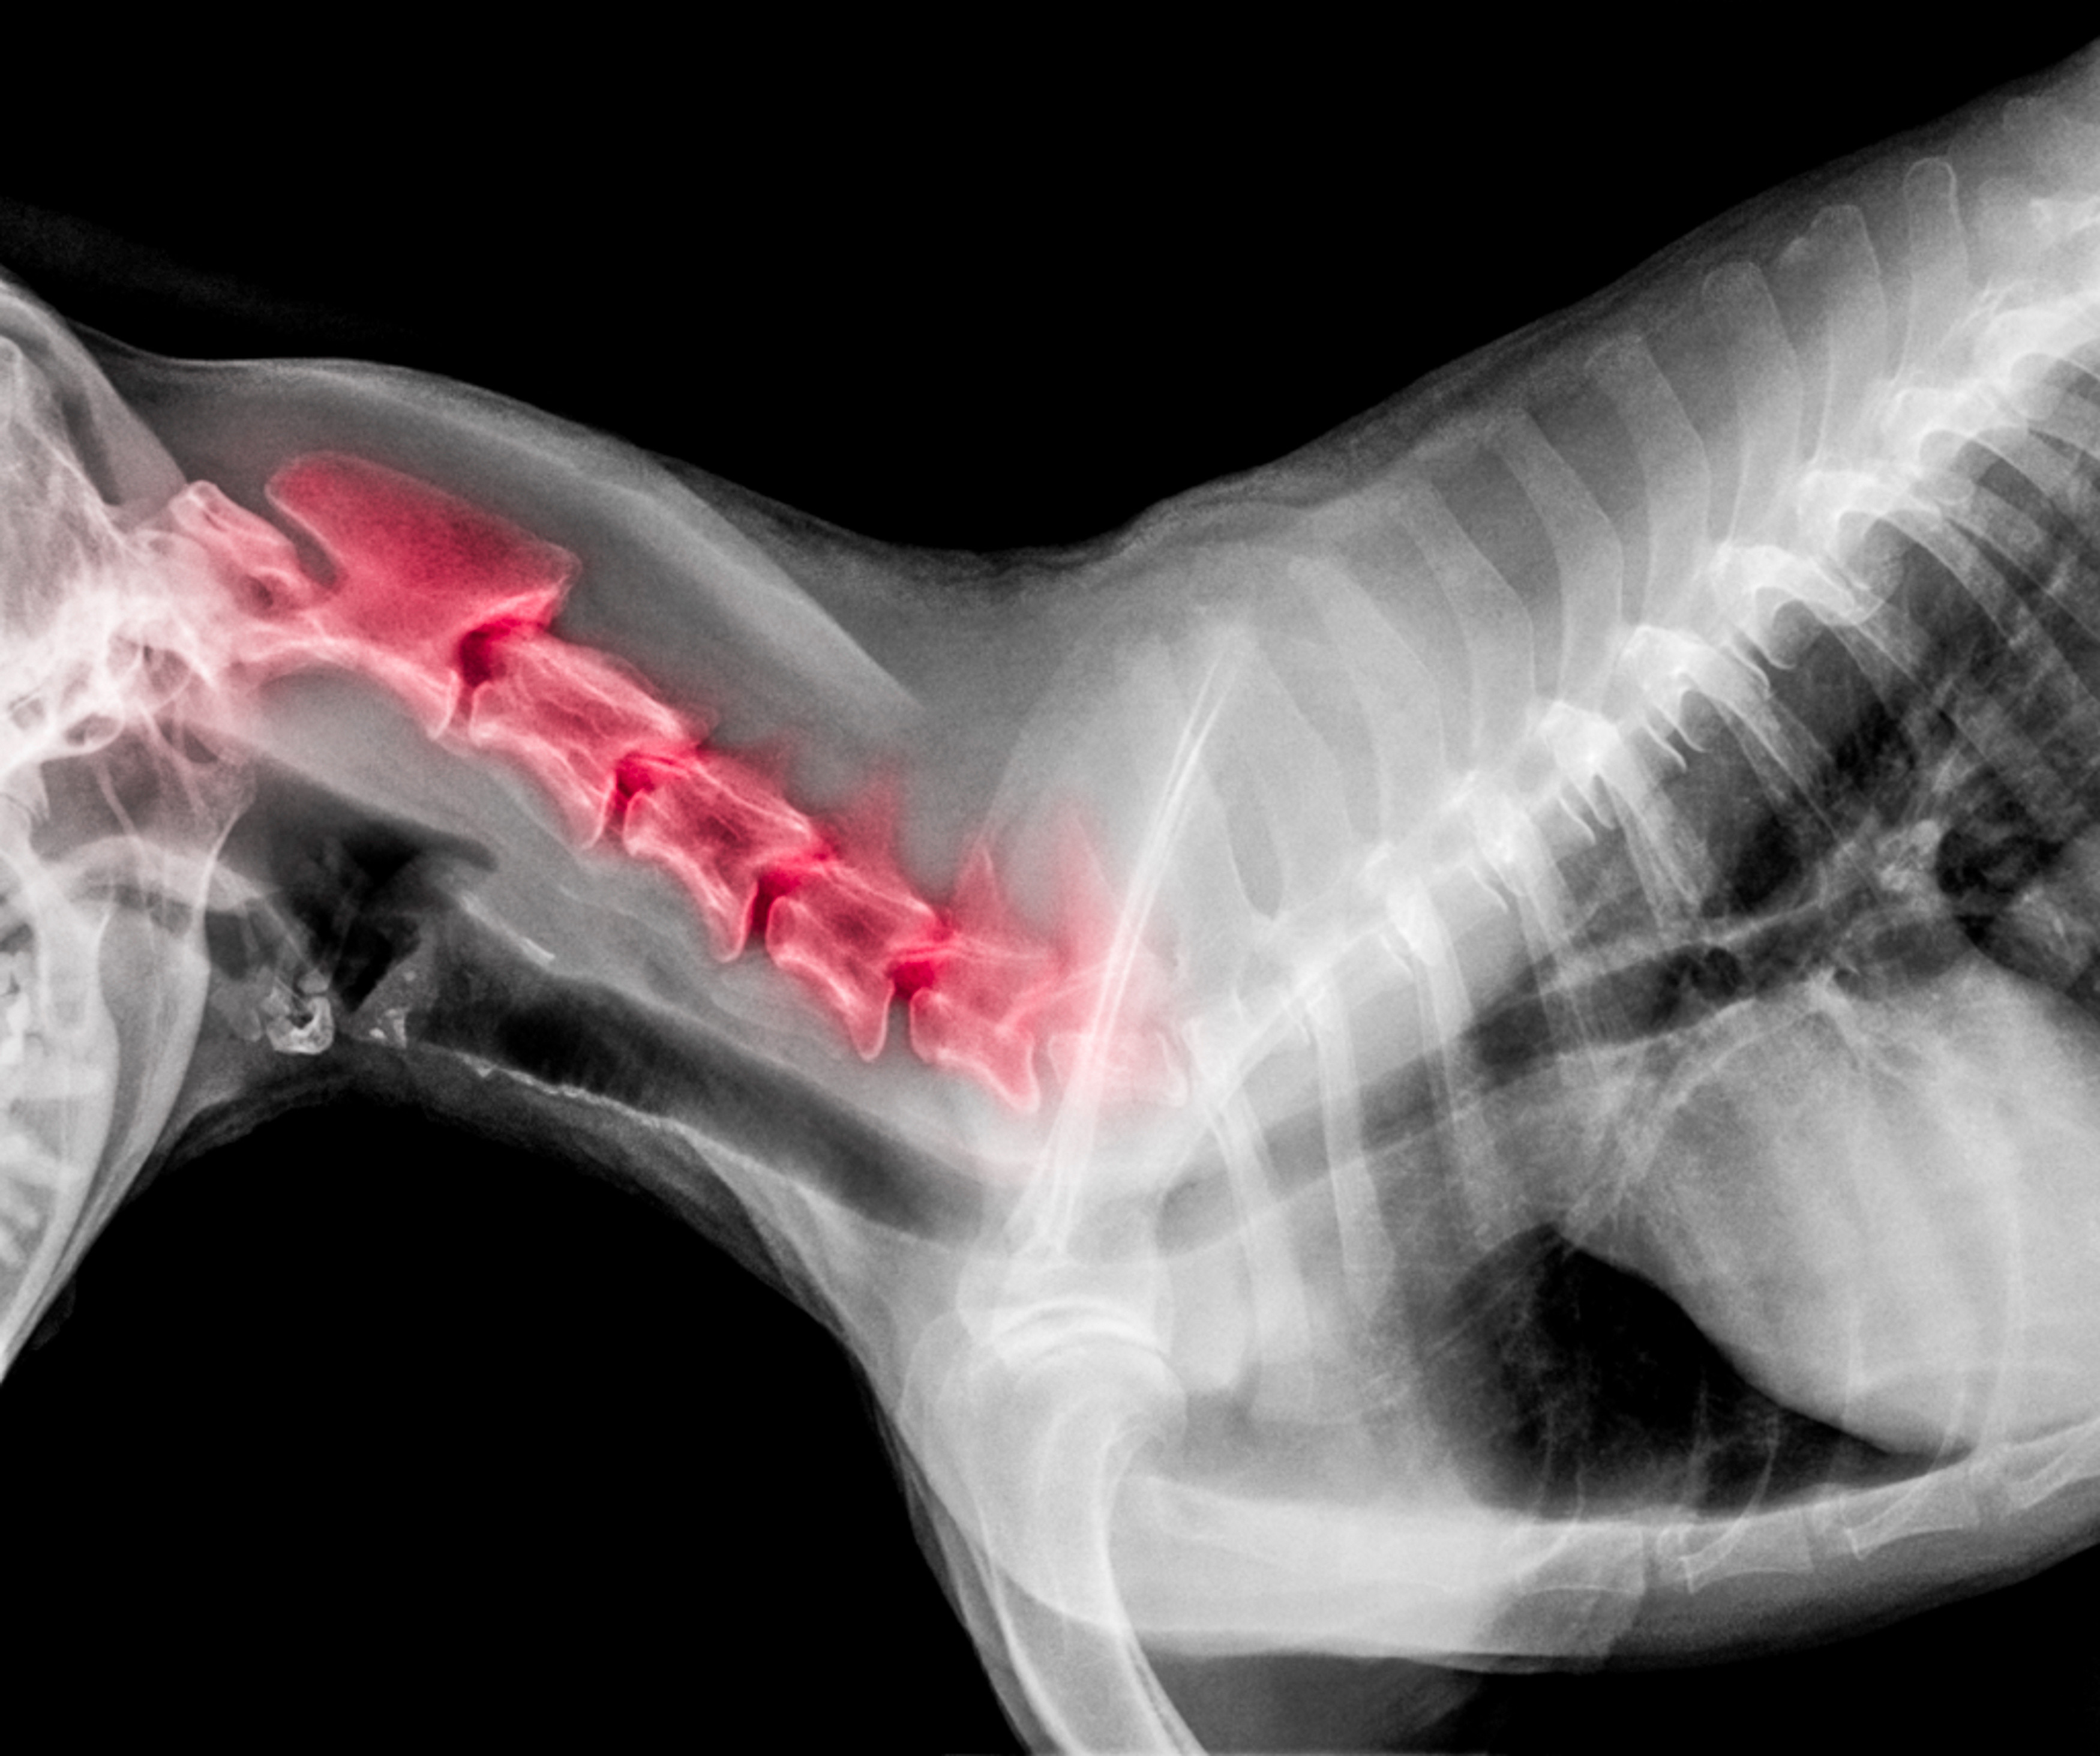

1. Spinal Cord Injury or Compression

⚠️ Very serious

Intervertebral Disc Disease (IVDD)

-

Herniated or ruptured discs

Trauma (jumping, falls, accidents)

Compression of the spinal cord interferes with signals to the legs, causing weakness or paralysis.

How Vets Diagnose Loss of Back-Leg Control

Your veterinarian may perform:

Neurological exam

X-rays or advanced imaging (MRI/CT)